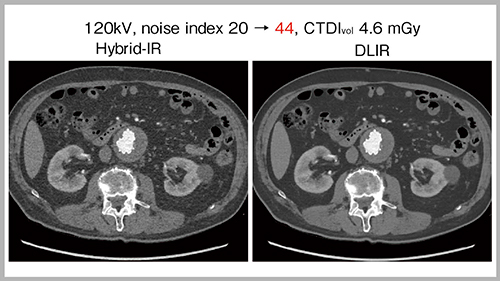

循環器領域においては,DLIRにてさらなる被ばく低減が期待できる。図1は,noise indexを20から44に上げ,被ばく線量を約80%低減した低線量CT画像である。本症例は,腹部大動脈へのステントグラフト内挿術後であるが,hybrid IRと比較してDLIRではノイズが少なく,ステント内血流の造影効果を十分な画質で評価できる。冠動脈においても同様に,解像度を劣化させることなく強力にノイズを抑制可能である。さらに,被ばく低減が重要となる小児領域では,CTDIvol 0.35mGyと非常に低線量でも,DLIRを用いることで,心臓内の構造や大血管がより明瞭に描出可能であった。

図1 低線量CT(80%減)におけるDLIRの有効性